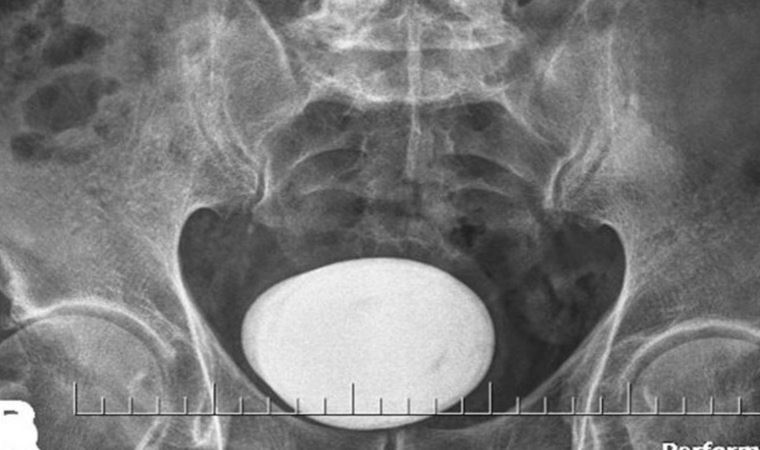

Yapılan tetkik ve tahliller sonucunda hastanın mesanesinde çok büyük bir taş saptandı.

Literatürde bu boyda taş görülmesi çok nadir karşılanırken hastanın mesanesinden çıkan taş şaşkınlıkla karşılandı. Derhal ameliyata alınan hastanın mesanesindeki taş kapalı yöntemle çıkarılması mümkün olmadığından açık sistolitotomi ameliyatı yapıldı.

Herkesi şaşkına çeviren büyük bir patates yumrusu şeklindeki taş başarılı şekilde alındı.